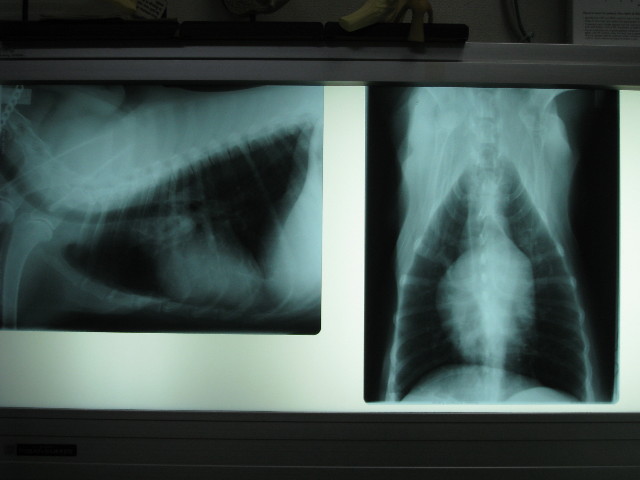

ベベはレントゲンなど撮ってなんやかんやステロイドを打ったのはお昼頃だった。